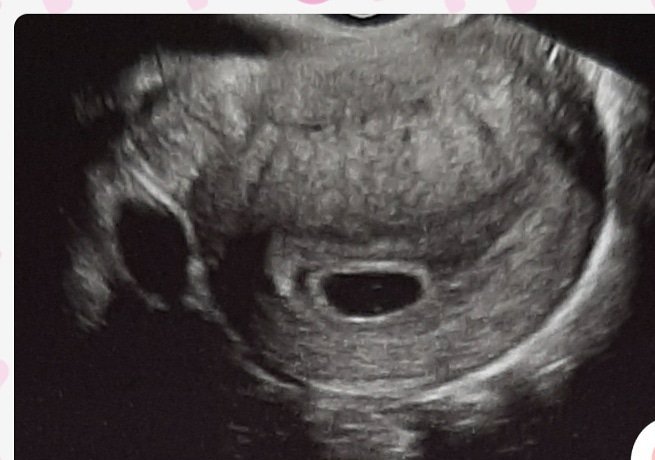

Mara ако са ти дали снимка от ехографа някъде по нея пише в коя г.с. си. Горе в дясно, долу в дясно потърси. При мен първия път също не видяха ембрион, а само плоден сак. Не се филмирай, важното е, че е в матката Simple Smile

Мара, с добро го казвам, стягай се, спри да се навиваш за лоши неща, че се искат доста сили ❤в 6г.с0дни си, по калкулатора който гледах,с термин 27. 04. 2021🍀Точно в 6г.с0дни ходих и имах само това

Изревах доста сълзи защо нямам ембрионче, но точно след 6дни(по мой спомен, че сега не мога да търся точно тефтера, където си пишех) имах ембрионче и пулс